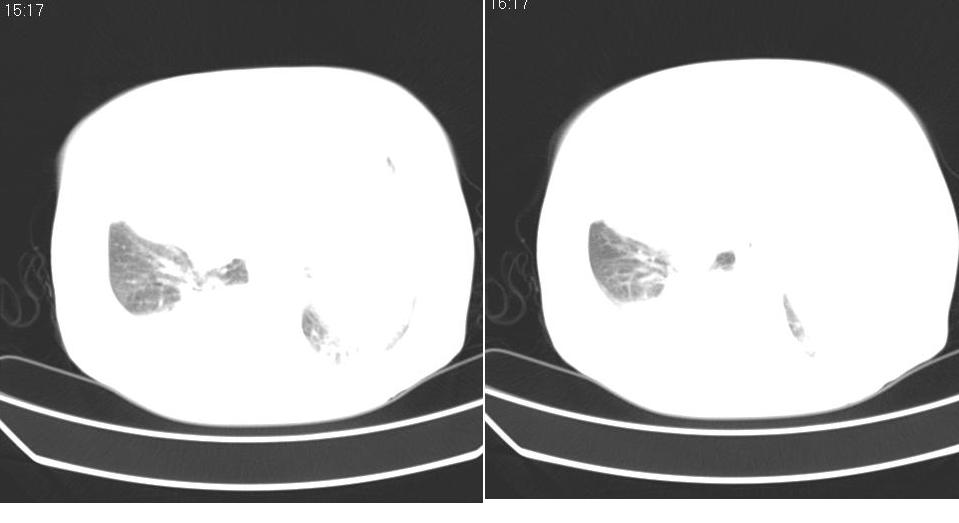

以下是引用liaizhi在2007-7-11 15:41:00的发言:[br]两肺纹理增粗,肺门影增大,气管支气管通畅。升主动脉壁及冠状动脉壁钙化。左房左室稍扩大。心包积液,胸腔积液。考虑冠心病并心功能不全,肺水肿,胸腔积液。

以下是引用zhangzhongshou在2007-7-11 13:16:00的发言:[br]1、冠状动脉钙化[br]2、心包积液[br]3、右侧胸腔积液[br]大家都考虑心衰,冠状动脉钙化、肺纹理增强,胸腔积液、心包积液,表面上是支持,但是为什么右侧有较多积液,左侧没有呢? 如果用结核性胸膜炎,并结核性心包炎也可解释,请楼主进一步提供临床资料。

以下是引用haha215315在2007-7-11 9:10:00的发言:[br]全心衰所致心包积液、胸腔积液、肺水肿。